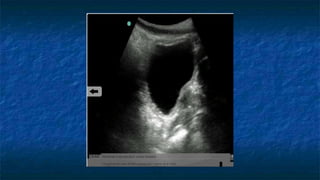

3)FAST: Pelvis exam

 Pelvis: Longitudinally and Transvers Axis.

 Probe placed

 Transeversally then Longitudinally

 Midline 2 cm superior to the symphysis pubis

 “aimed” caudally into the pelvis (prostate )

 Probe facing

 Toward patient’s head and right side.

 Best with some urine in bladder(acoustic window)

 Evaluating

 Bladder ,Uterus in female ,and Prostate in

male

 The potential spaces are Pouch of

Douglas (Cul de sac ) in female and

retrovesicle space in male

FAST: Pelvis exam

 Pelvis: Transverse Axis

 Normal Anatomy

 Evaluating Bladder

 Well cirucumscribed

 Contains fluid that

appears anechoic

FAST: Pelvis exam - Pathology

Transverse

Bladder

FF